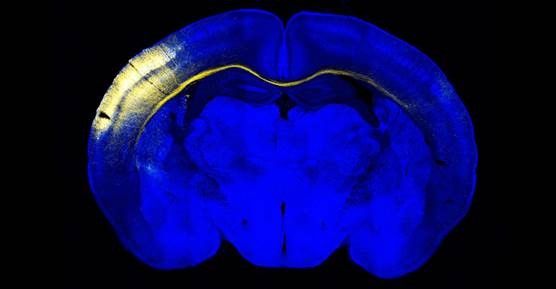

Investigadoras del Centro Nacional de Biotecnología del Consejo Superior de Investigaciones Científicas (CSIC) han comprobado que el cerebro tiene mayor plasticidad de la que se pensaba durante la infancia, lo que les ha permitido identificar nuevos mecanismos que generan “circuitos cerebrales alternativos” durante el desarrollo del cerebro.

Según informó este martes el CSIC, los resultados de este trabajo publicados en la revista ‘Nature Communicatios’, demuestran que el cerebro tiene mayor plasticidad durante la infancia y la adolescencia, ya que favorece aquellos circuitos con una mayor funcionalidad ante situaciones adversas o la carencia de estímulos, como la expansión de los sentidos del oído y el tacto en los ciegos de nacimiento.

Ambos hemisferios están conectados mediante el cuerpo calloso, “una autovía de intercambio de información” que se desarrolla durante la infancia y la adolescencia.

Para ello, han analizado en ratones los circuitos interhemisféricos que procesan la información sensorial del exterior en un grupo de neuronas considerado hasta ahora como el paradigma de neurona local, la cual recibe la información sensorial a través del tálamo.